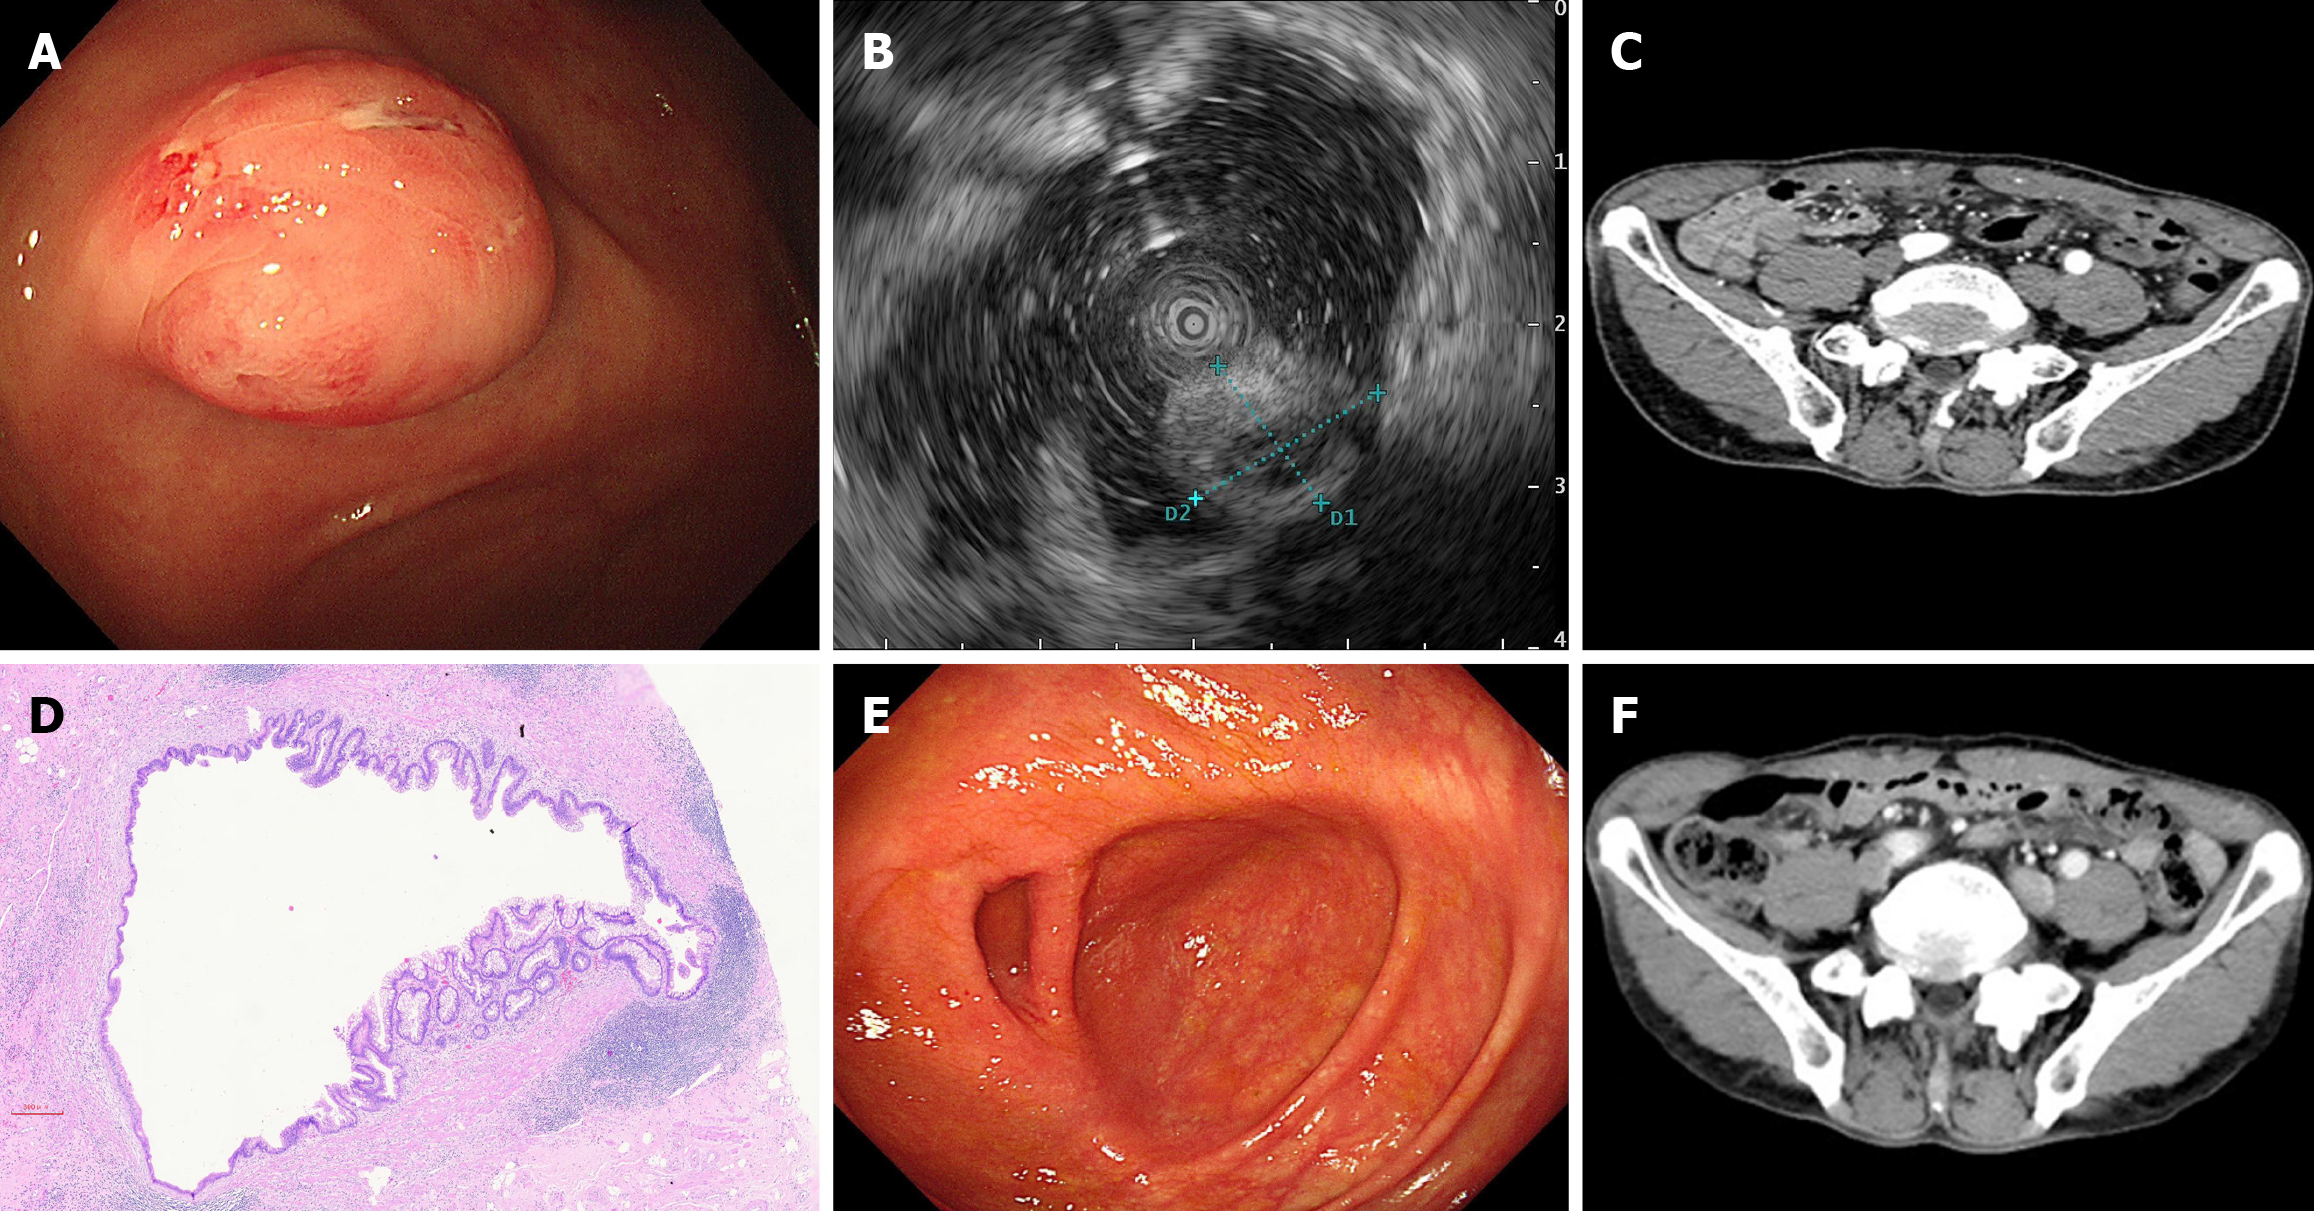

Colonoscopy revealed a submucosal protrusion at the opening of the appendix (Figure 1A). During endoscopic ultrasound, uneven echoes were observed in the appendix cavity (Figure 1B). A contrast-enhanced computed tomography (CT) scan of the abdomen revealed a nodular thickening at the base of the appendix, with a diameter of approximately 1 cm (Figure 1C).

Postoperative pathology revealed a low-grade mucinous cystadenoma of the appendix with no involvement of the margins (Figure 1D).

The patient recovered well after surgery. A repeat colonoscopy 18 months after surgery revealed no significant abnormality at the appendiceal orifice (Figure 1E). A contrast-enhanced CT scan of the abdomen suggested only postoperative changes (Figure 1F).